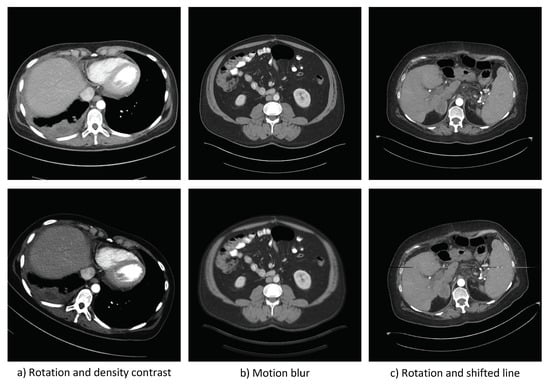

The first step is to determine the transformations to be applied to the images in the source dataset to generate the follow-up test cases. These transformations are then randomly applied to images from the source dataset in order to generate the follow-up test cases in proportions similar to the frequency of the target circumstances. We call this newly generated dataset of follow-up test cases, the target dataset. See Figure 6 for examples of source and follow-up test cases, for the MDS case.

Figure 6.

Examples of source test cases (source circumstances), on the top, and follow-up test cases (target circumstances), on the bottom, for the MDS case.